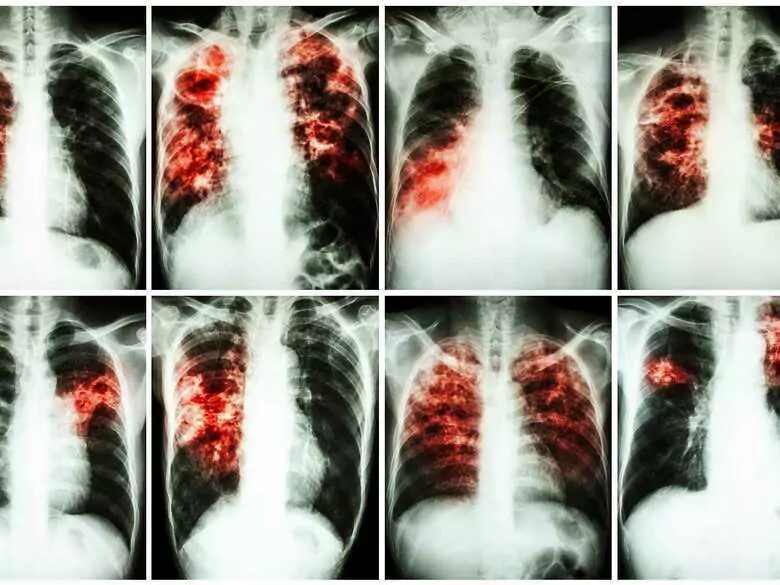

Według Krajowego Rejestru Nowotworów, co roku w Polsce 22 tysiące osób słyszy diagnozę: rak płuca, a według prognozy na 2025 rok zachorowalność wzrośnie do około 23,5 tysiąca. Niestety liczba zgonów związanych z tą chorobą jest zbliżona do liczby zachorowań. Jedynie ok. 15-20 proc. chorych jest diagnozowanych we wczesnym stadium co oznacza, że blisko 80 proc. nowych rozpoznań dotyczy chorych z bardzo złym rokowaniem. Najczęstszą przyczyną raka płuca jest nadal czynne i bierne palenie papierosów. Ok. 90 proc. chorych to osoby, które były narażone na działanie szkodliwych składników dymu tytoniowego.